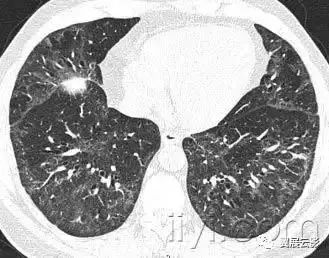

三十八、粟粒样

平片和CT:在胸片上,粟粒样代表大量小的、分散的、圆形肺部阴影(直径小于3mm),大小相对均以一致,双肺内弥漫性分布。是结核或者转移性病变弥漫性分布的特征。薄层CT上显示为广泛、随机分布的微结节。